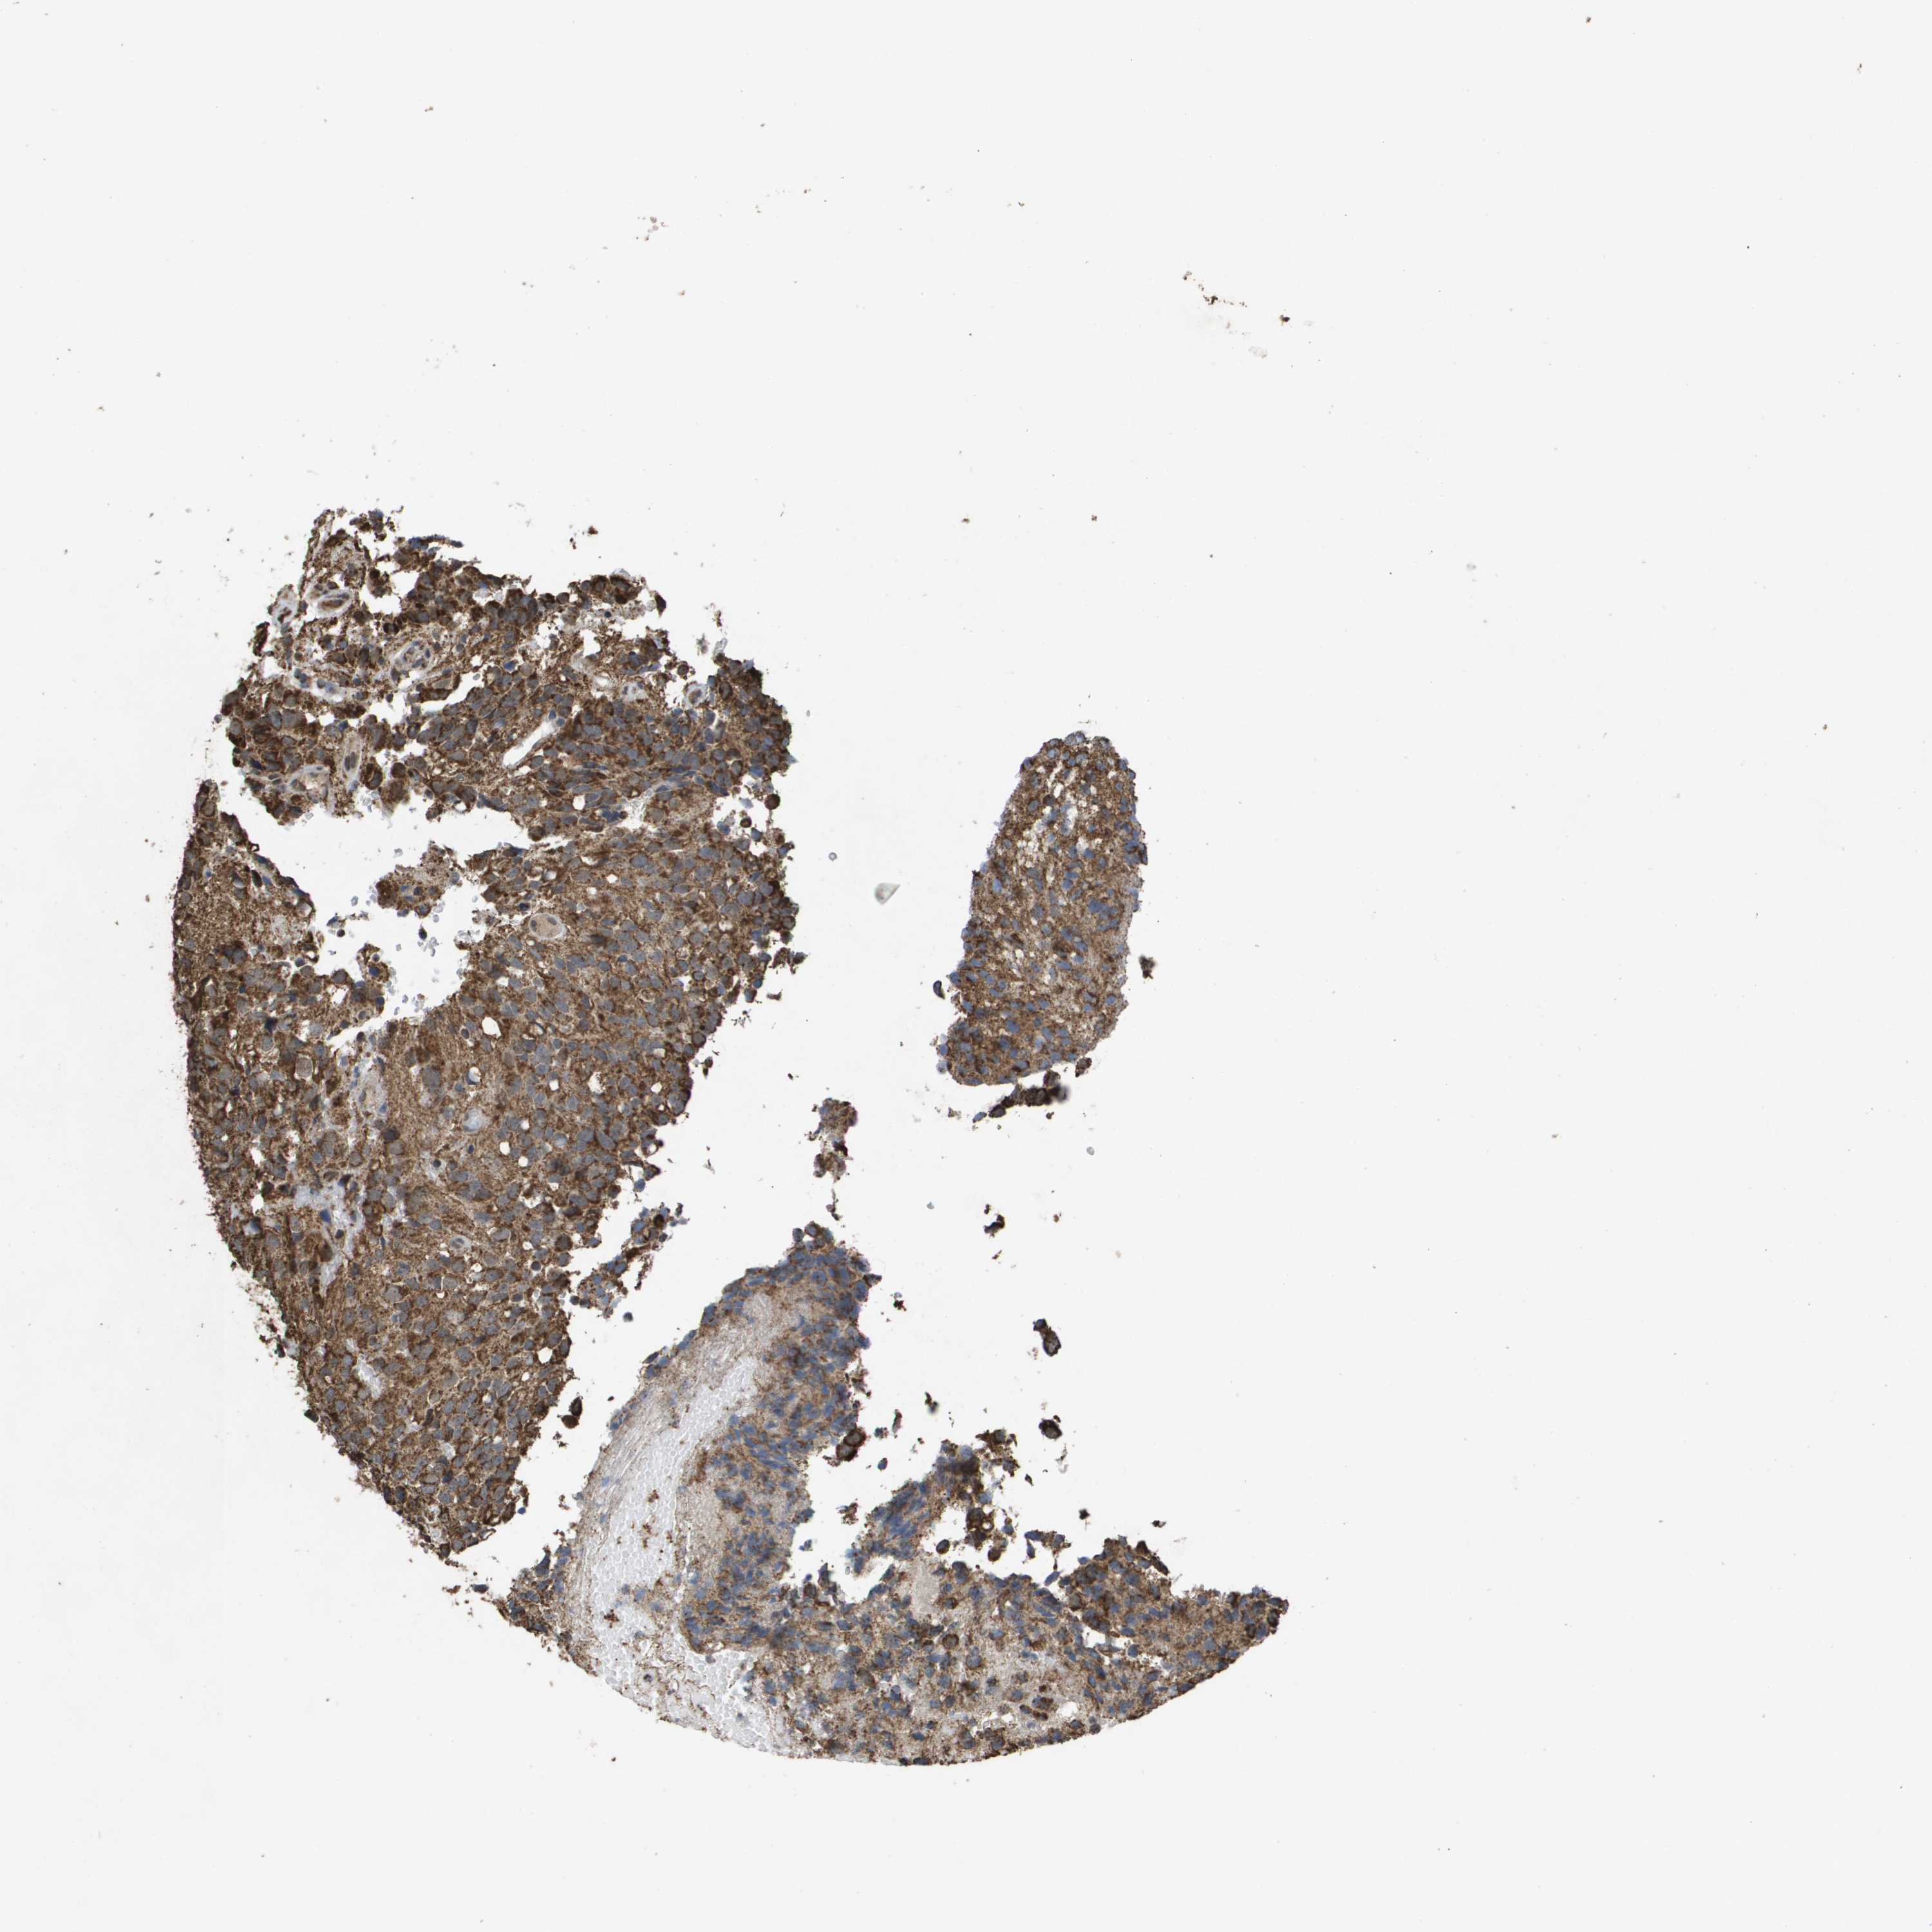

GLIOMA - Protein expressioni

A mouse-over function shows sample information and annotation data. Click on an image to view it in a full screen mode. Samples can be filtered based on level of antibody staining by selecting one or several of the following categories: high, medium, low and not detected. The assay and annotation is described here.

Note that samples used for immunohistochemistry by the Human Protein Atlas do not correspond to samples in the TCGA dataset.

Antibody stainingi

Antibody staining in the annotated cell types in the current human tissue is reported as not detected, low, medium, or high, based on conventional immunohistochemistry profiling in selected tissues. This score is based on the combination of the staining intensity and fraction of stained cells.

Each image is clickable and will lead to virtual microscopy that enables deeper exploration of all samples and also displays staining intensity scores, fraction scores and subcellular localization as well as patient and tissue information for each sample.

Antibody HPA038755

Antibody HPA048272

Antibody CAB017366

Staining

High

Medium

Low

Not detected

Intensity

Strong

Moderate

Weak

Negative

Quantity

>75%

75%-25%

<25%

None

Location

Nuclear

Cytoplasmic/membranous

Cytoplasmic/membranous,nuclear

Glioma, malignant, High grade

Glioma, malignant, Low grade

Glioblastoma, NOS